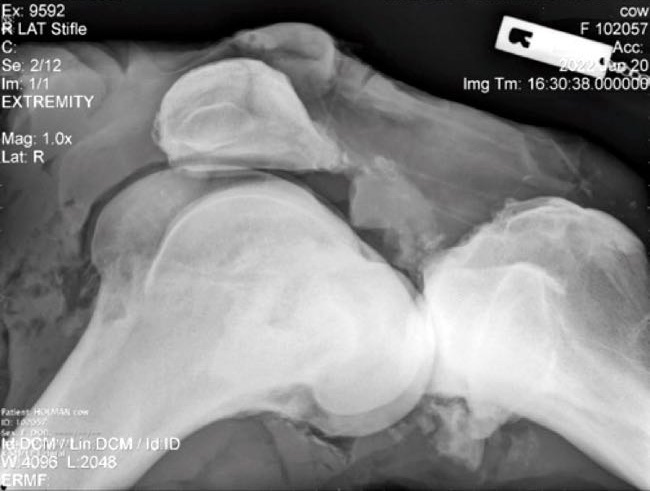

Xray of bovine stifle with lumpy bits

Head to the article to find out if you are correct.